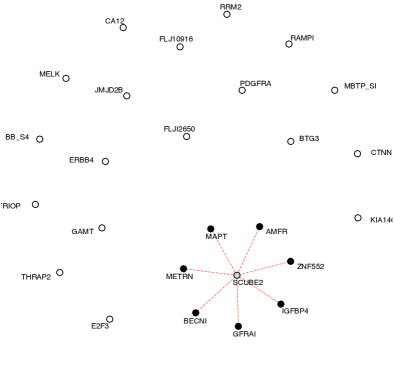

Figure 3 plots the resulting networks obtained for three different penalizations. The penalization parameters were heuristically chosen from the number of expected nonzero entries. We used latent clusters, and it is interesting to note that when assuming more than two clusters, the algorithm systematically produces exactly two non-empty clusters.

The inferred networks exhibit very different structures according to the class of patients. This in itself is interesting and suggests that gene regulation differs with respect to the presence or absence of a pCR.

The network obtained with not-pCR cases displays a two-star pattern. Each star connects to a unique gene, either SCUBE2 or IGFBP4. Almost all the most significant connections imply SCUBE2. This star pattern suggests that further studies of this particular gene would be of interest for understanding residual disease.

The network estimated with the pCR cases has a different two-cluster structure. In particular, it groups IGFBP4 and SCUBE2 in the same cluster with a direct significant link. This again indicates a completely different relationship between the genes in pCR versus non-pCR.

| not-pCR | pCR | |

|---|---|---|

|

Low penalty |

|

|

|

Medium penalty |

|

|

|

High penalty |

|

|